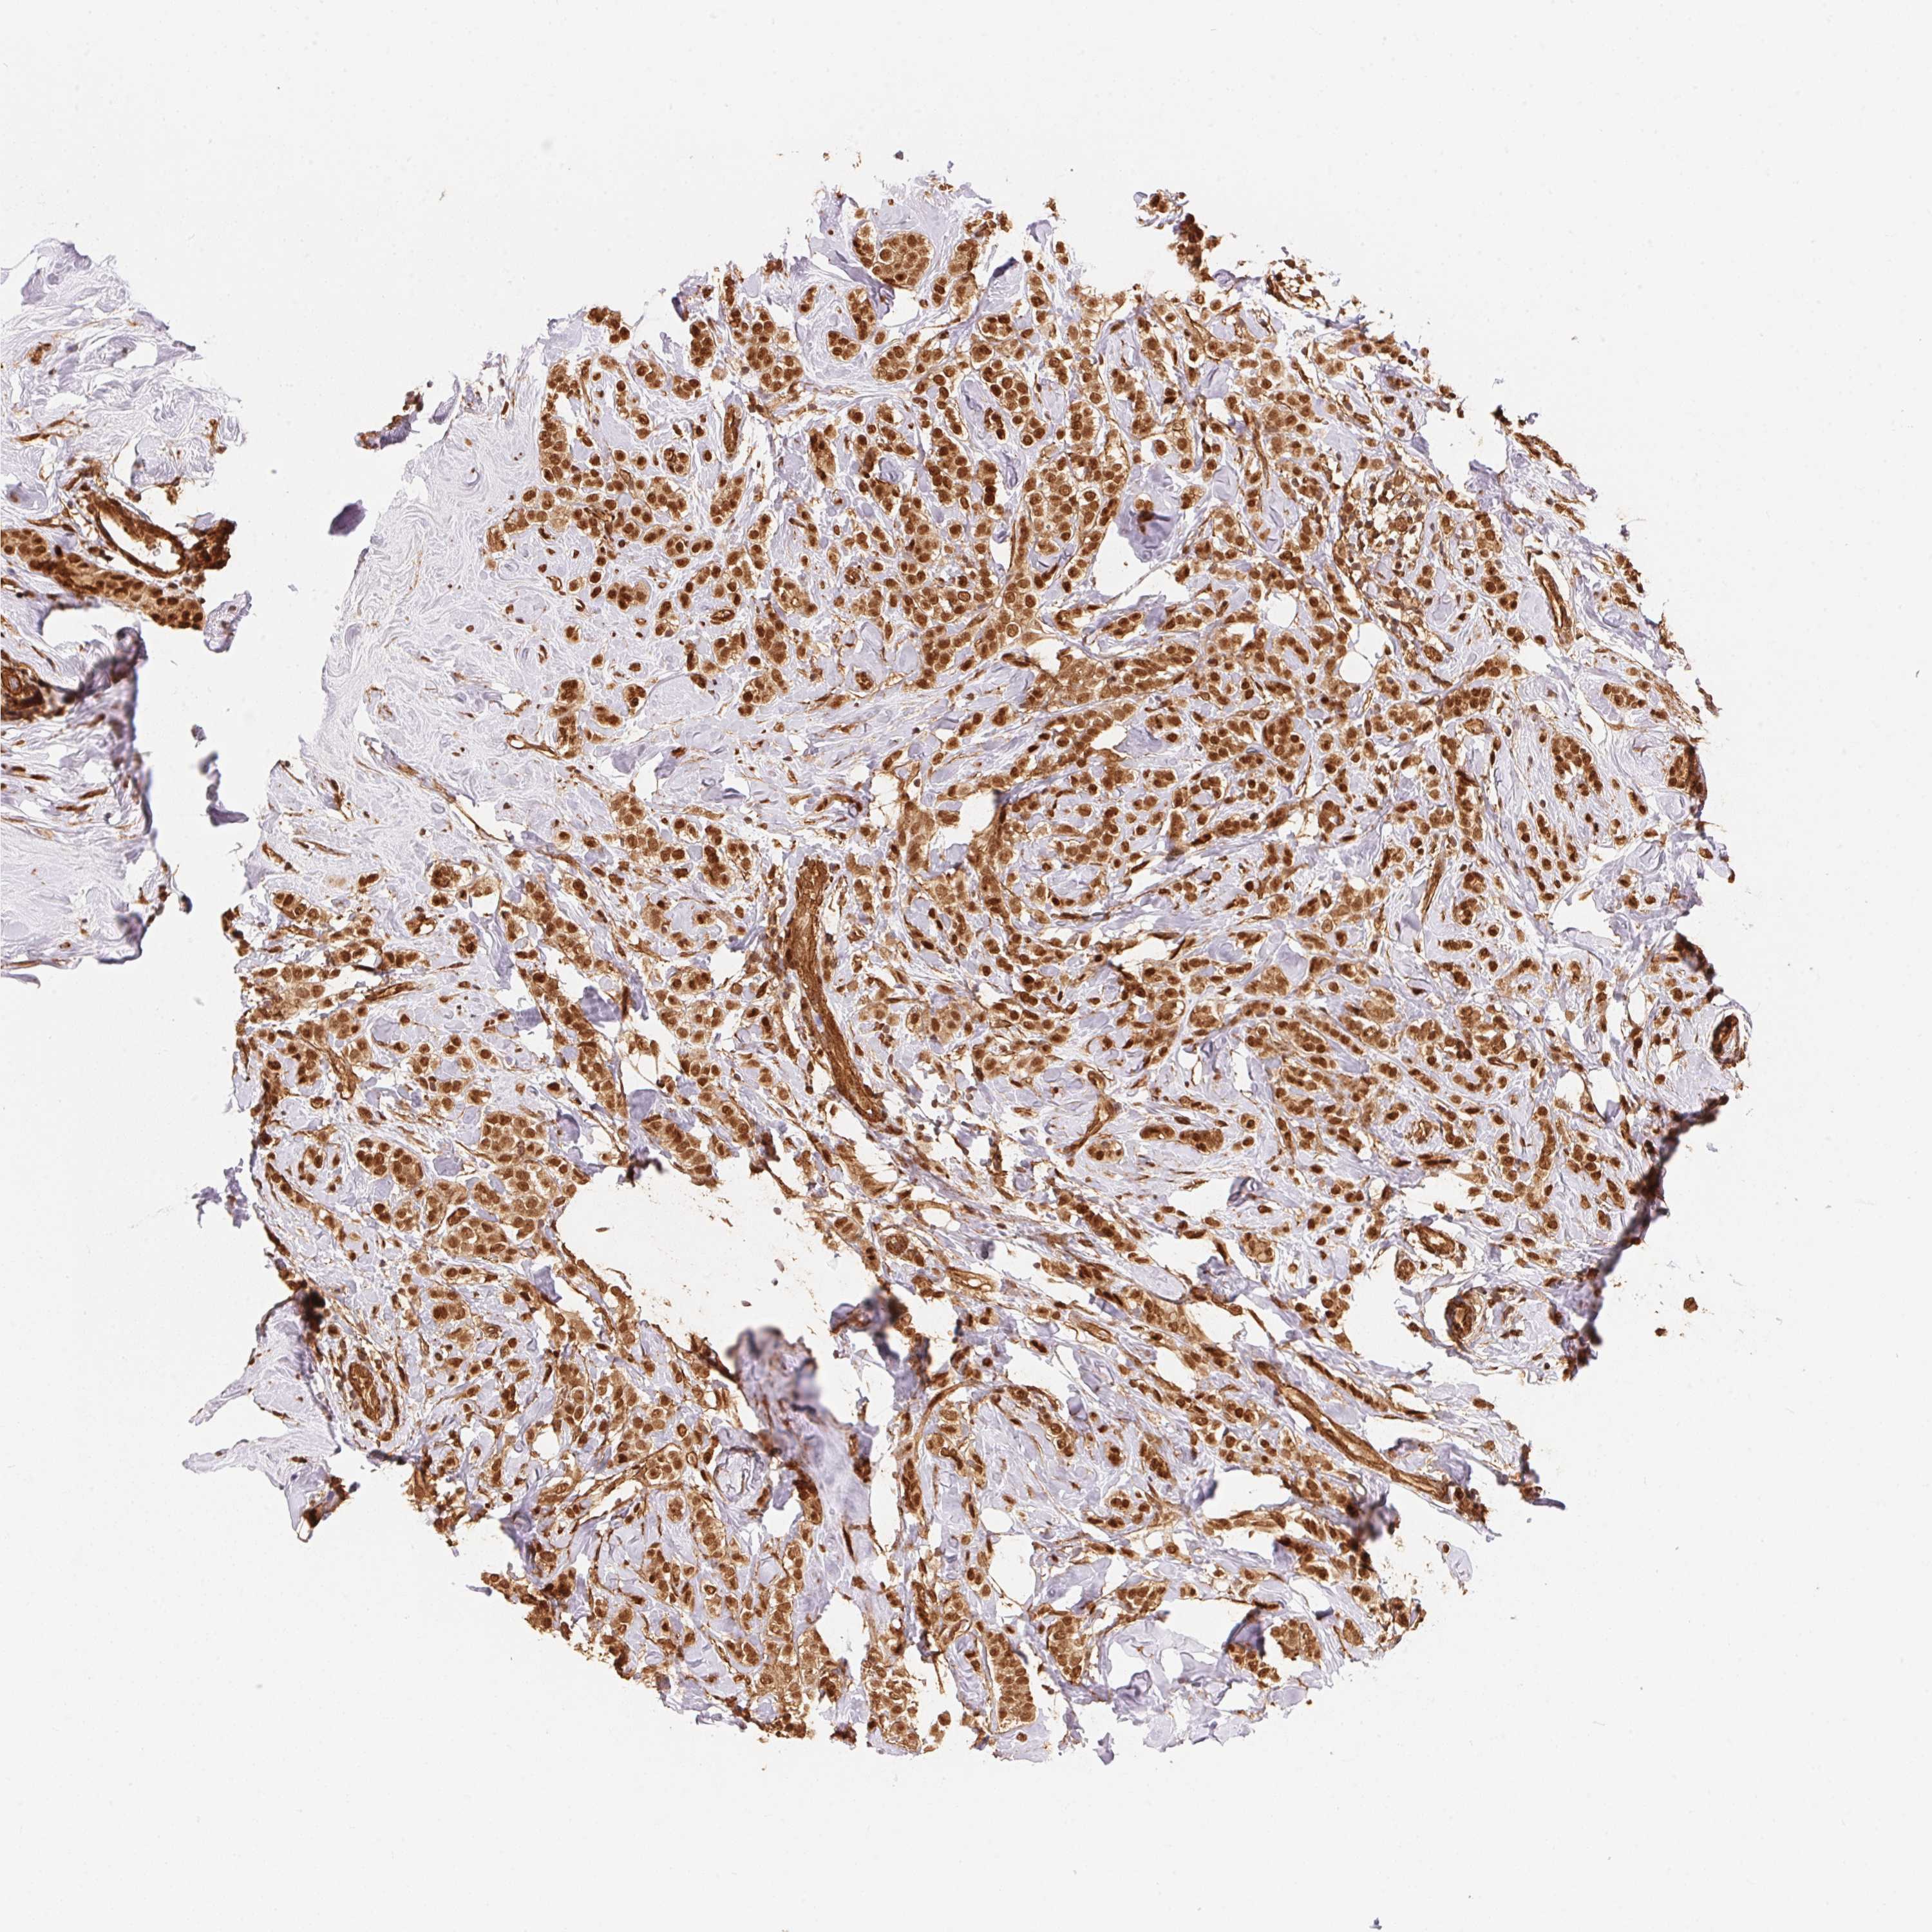

CANCER BREAST CANCER Show tissue menu

BRCA TCGA BRCA VALIDATION PROTEIN EXPRESSION

ANTIBODIES

AND

VALIDATION